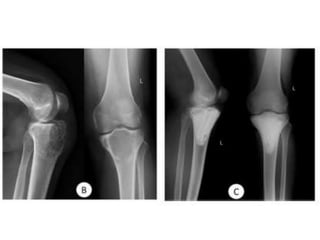

CASE 2

CASE 3

CASE 4